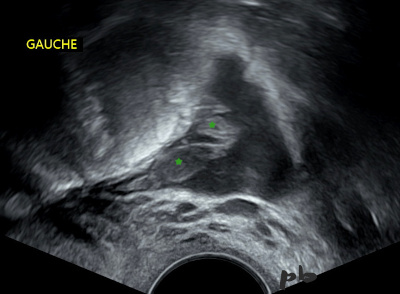

4-GEU – Pseudo sac gestationnel

- Hématométrie (★)

Elle est bordée par une seule couche hyperéchogène (caduque).

-

Un sac gestationnel est toujours bordé par 2 couches hyperéchogènes, caduques et trophoblaste, dont l’échogénicité est un peu différente, permettant de les différencier.

Myomètre en-dehors.